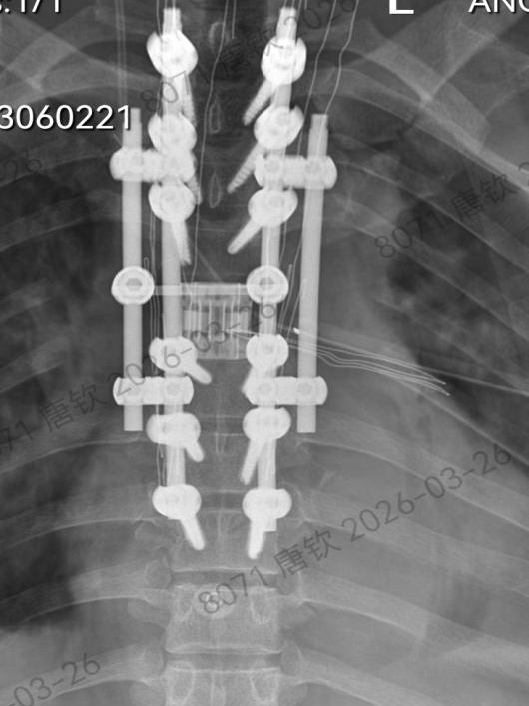

手术过程中,在脊柱外科团队戴楠主任医师、周远哲主治医师、喻博住院医师的紧密辅助配合下,唐钦主任医师沉着执刀、精准操作,在毫米级空间内精细操作、步步为营。术者凭借深厚的技术功底与极强的心理素质,完整剥离并整块取出肿瘤及受累椎体;面对脊柱稳定性重建这又一难题,团队采用目前国内最先进的3D打印人工椎体精准植入填充,配合椎弓根钉系统牢固固定,完美重建脊柱力学结构,全程实现脊髓零牵拉、零损伤,创下极限操作下的手术奇迹。

术后复查影像检查图像